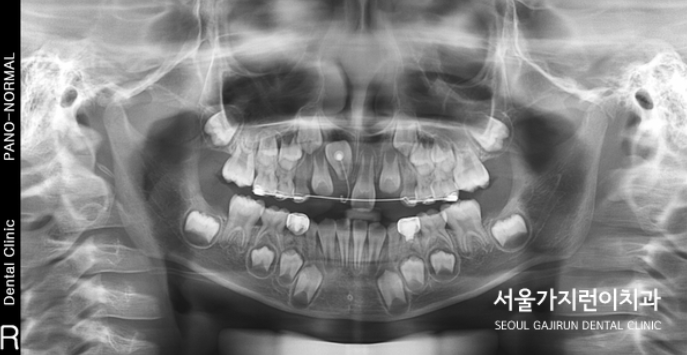

엑스레이를 통해 더 확실히 확인할 수 있는 중절치

환자의 경우 눈으로 봤을 때는 자연스런 증상인것처럼 보이지만 엑스레이 화면으로 봤을 때는 상악 앞니가 180도로 돌아간 상태인 것을 확인할 수 있었는데요. 거꾸로 치아가 숨어있는 상태로 공간 확보가 별도로 필요하지 않은 상태에 치과를 방문해주었습니다. 이런 경우는 치아의 뿌리가 짧기 때문에 치근 흡수의 가능성도 보여 매복치의 견인을 이끌어주는 교정을 진행해야 했는데요.